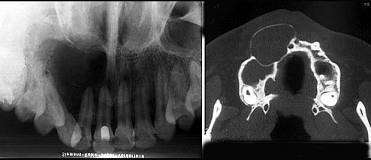

位于上颌侧切牙与尖牙之间的非牙源性囊肿(影像检查如图)是 ( ) A.球上颌囊肿 B.正中囊肿 C.鼻唇囊肿 D.鼻腭囊肿 E.角化囊肿

问题 位于上颌侧切牙与尖牙之间的非牙源性囊肿(影像检查如图)是 ( )

选项 A.球上颌囊肿 B.正中囊肿 C.鼻唇囊肿 D.鼻腭囊肿 E.角化囊肿

答案 A